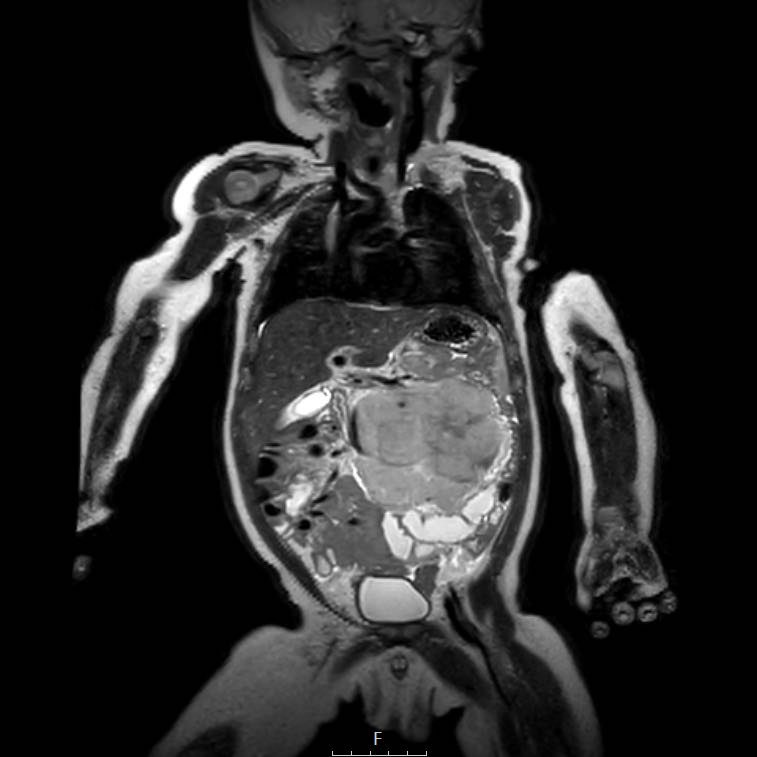

Hình ảnh MRI của một bé gái chín tháng tuổi có khối u ở bụng trái. MRI cho thấy khối u tuyến thượng thận trái, một phần đặc, một phần nang. Có nhiều di căn gan.

Khối u đã được sinh thiết. Có tình trạng chảy máu liên tục qua kim dẫn đường. Vào cuối thủ thuật, hai nút bọt gelatin đã được đặt vào (các dải tăng âm (mũi tên)).